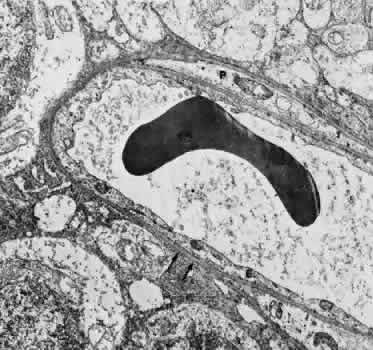

The capillaries and venules of the ciliary body are 15 to 30 μm in diameter and are fenestrated in both the pars plicata and pars plana. They closely resemble the capillaries of the choriocapillaris except that they are smaller. The fenestrae of these vessels range in size from 300 to 1,000 nm in diameter.64 The major difference between the capillaries in different areas of the ciliary body is that only those of the pars plana are in contact with the elastica of Bruch's membrane on the surface facing the pigmented epithelium. The capillaries present in the ciliary muscle are nonfenestrated (Figs. 16 and 17). The blood vessels are innervated by small branches of sympathetic fibers.

Fig. 16. Electron micrograph of a portion of a capillary facing the stroma of the ciliary process. The endothelial cell contains moderate amounts of rough-surfaced endoplasmic reticulum and numerous pinocytotic vesicles and few fenestrae. A very thin basement membrane is present. Particles of thorium dioxide may be seen in the lumen (l). This specimen was taken from a rat.

Fig. 17. Electron micrograph of a portion of a capillary from the ciliary process facing the pigmented epithelium (p). Note the absence of an elastic lamina between the vessel and the pigmented epithelium. Fenestrae are present, and the endothelium is quite attenuated. This specimen was taken from a rat injected with thorium dioxide. l, capillary lumen.